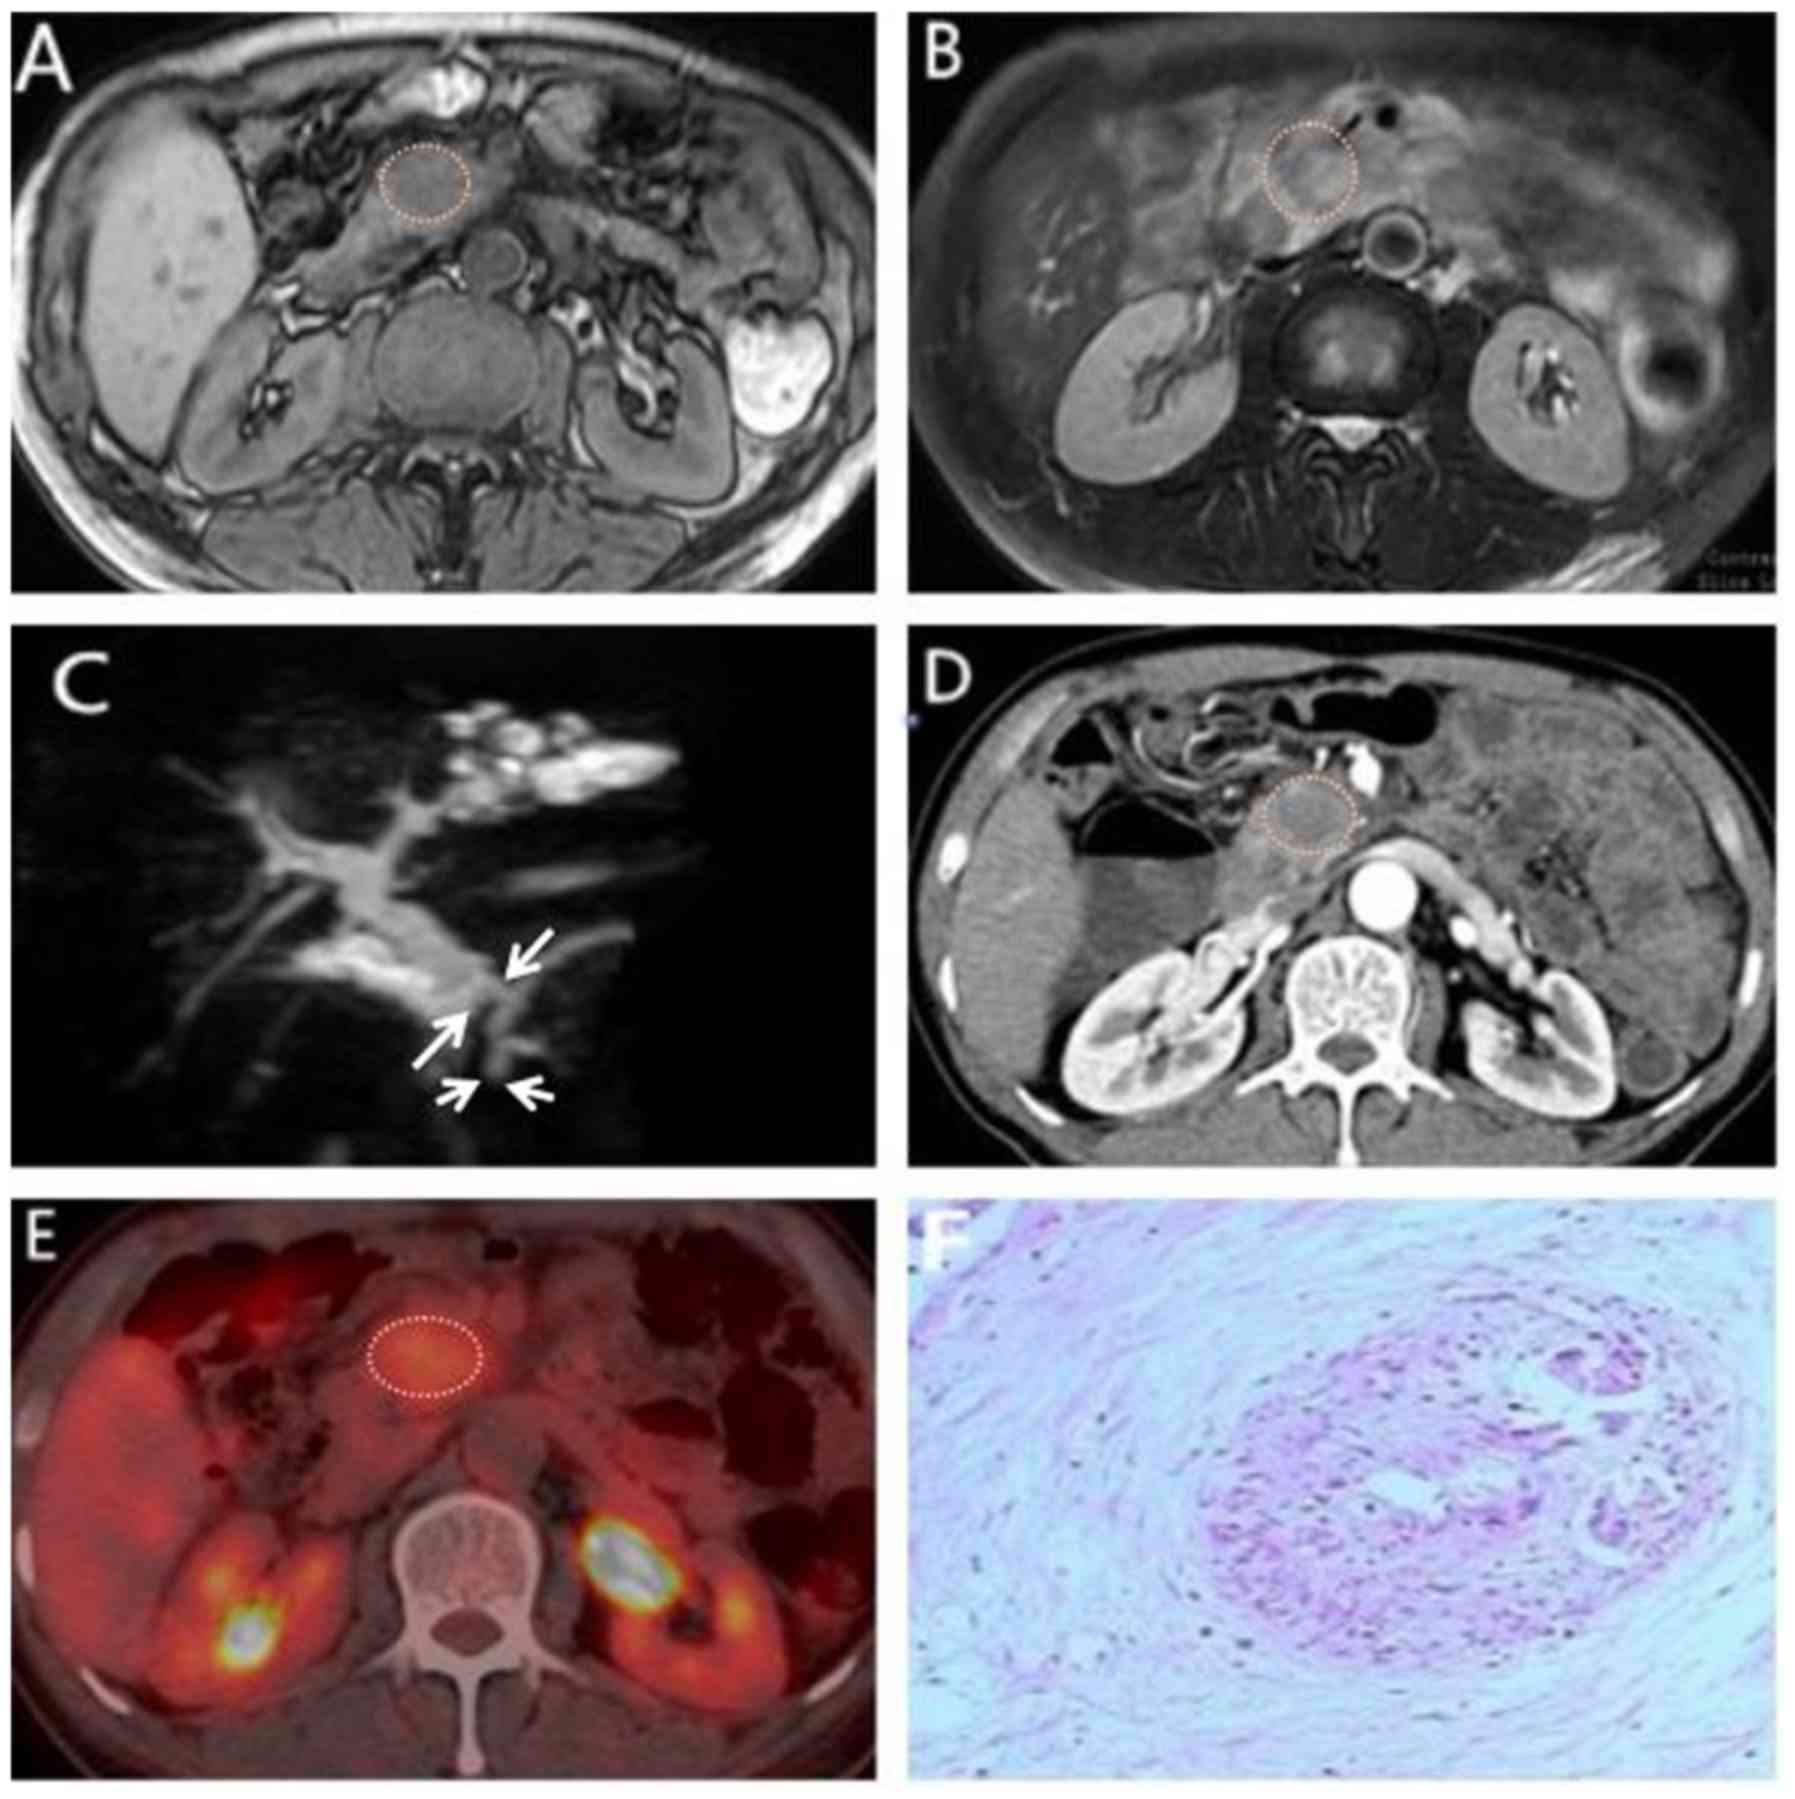

Pdf Comparison Of Mdct Mri And Mri With Diffusion Weighted

Comparison Of Mdct Mri And Mri With Diffusion Weighted Imaging In